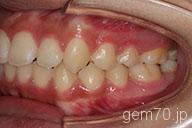

症状:叢生装置:セラミックブラケット | 非抜歯(歯を抜かない)世代:中学生

主訴)歯のでこぼこ

診断)叢生

年齢)14歳

使用装置)マルチブラケット装置

治療方法)非抜歯(歯を抜かない)

治療期間) 2年4ヵ月 通院回数 27回